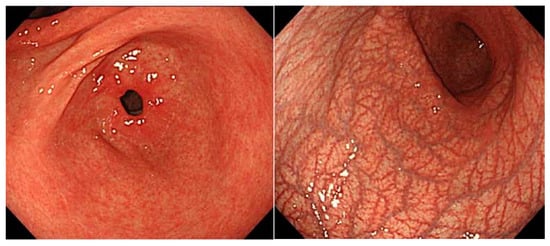

5. Findings of Early AIG

- Ayaki, M.; Aoki, R.; Mastunaga, T.; Manabe, N.; Fujita, M.; Kamada, T.; Kobara, H.; Masaki, T.; Haruma, K. Endoscopic and Upper Gastrointestinal Barium X-ray Radiography Images of Early-stage Autoimmune Gastritis: A Report of Two Cases. Intern. Med. 2021, 29, 1691–1696. [Google Scholar] [CrossRef]

- Kishino, M.; Yao, K.; Hashimoto, H.; Nitta, H.; Kure, R.; Yamamoto, A.; Yamamoto, K.; Nonaka, K.; Nakamura, S.; Tokushige, K. A case of early autoimmune gastritis with characteristic endoscopic findings. Clin. J. Gastroenterol. 2021, 14, 718–724. [Google Scholar] [CrossRef]

- Kotera, T.; Oe, K.; Kushima, R.; Haruma, K. Multiple Pseudopolyps Presenting as Reddish Nodules Are a Characteristic Endoscopic Finding in Patients with Early-stage Autoimmune Gastritis. Intern. Med. 2020, 59, 2995–3000. [Google Scholar] [CrossRef]

- Kotera, T.; Yamanishi, M.; Kushima, R.; Haruma, K. Early autoimmune gastritis presenting with a normal endoscopic appearance. Clin. J. Gastroenterol. 2022, 15, 547–552. [Google Scholar] [CrossRef]